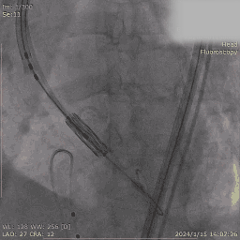

Step 6. 复查造影示瓣膜支架膨胀良好,少量瓣周漏

Step 7. Proglide闭合主入路股动脉,造影确认未见明显狭窄、渗漏